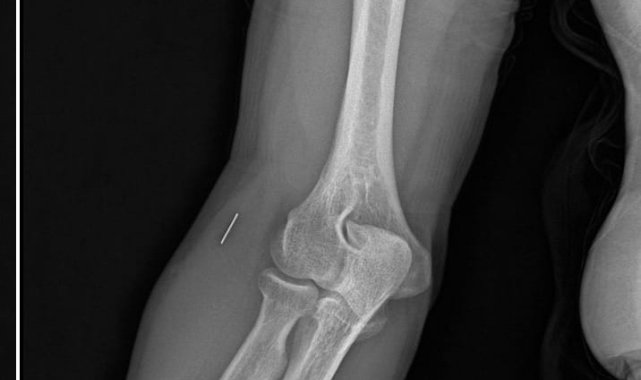

Kocaeli'de Kurban Bayramı'nda yaşadığı bıçak kesiğinin ardından başvurduğu iki özel hastanedeki yanlış tedavi iddiaları sebebiyle parmağı ampute edilen ve çalışma kabiliyetini kaybederek işinden olan Nurettin Güleryüz, "tıbbi ihmal" iddiasıyla tedaviyi yürüten doktorlar hakkında suç duyurusunda bulundu.Edinilen bilgiye göre, 7 Haziran 2025'te Kurban Bayramı dolayısıyla bıçak temizlerken sağ el başparmağını kesen Nurettin Güleryüz (34), bir özel hastanenin acil servisine başvurdu. İddiaya göre, hastanede detaylı tetkik yapılmadan pansuman uygulanan Güleryüz'e ilaç reçete edilerek taburcu edildi. Şikayetlerinin devam etmesi ve kanamanın durmaması üzerine ertesi gün aynı hastaneye tekrar giden Güleryüz'e bu kez dikiş atıldı.Parmağını hareket ettirememesi üzerine 19 Haziran'da Gebze'deki başka bir özel hastaneye başvuran Güleryüz, tendon yaralanması şüphesiyle tedaviye alındı. Farklı tarihlerde yapılan EMG ve MR tetkiklerinde sinir hasarı ile tendon kopması tespit edilen hasta, 2 Eylül'de ameliyat edildi. Süreç içerisinde parmağın çürüdüğü ve kurtarılamayacağının belirtilmesi üzerine Güleryüz, başvurduğu başka bir hastanede ampute operasyonu geçirdi.Öte yandan, ameliyatların ardından ağrıları devam eden Güleryüz'ün kolunda metal parça bulunduğu ve bu parçanın parmak bölgesinden dirseğe doğru ilerlediği öne sürüldü. Ayrıca, fabrikada temizlik personeli olarak çalışan Nurettin Güleryüz'ün hastane sürecinde işten çıkarıldığı da öğrenildi."Yüzde 46 olan engellilik oranı yüzde 75'e yükseldi"Güleryüz'ün avukatı Barış Kurt, Gebze Cumhuriyet Başsavcılığına sunduğu şikayet dilekçesinde, özel hastanede görevli hekimlerin tıp kurallarına aykırı hareket ederek ihmalde bulunduklarını ileri sürdü. Olayın basit tıbbi komplikasyon olmadığını savunan Kurt, "Başparmakta oluşan kesilerde tendon ve sinir hasarı ihtimali basit muayene ile dahi anlaşılabilecek durumdur. Buna rağmen şüpheli hekimler gerekli özeni göstermemiştir. Doğru teşhis zamanında konulmuş olsaydı, gerekli cerrahi müdahale gecikmeden yapılacak ve müvekkil kalıcı sakatlık yaşamayacaktı. Müvekkilin yaralanma öncesinde yüzde 46 olan engellilik oranı, yaşanan süreç sonrası yüzde 75'e yükselmiştir. Bu durum müvekkilin yaşamını ve çalışma gücünü ciddi şekilde etkiledi. Sorumlular hakkında taksirle yaralama, görevi kötüye kullanma ve ihmali davranışla yaralama suçlarından soruşturma yürütülmesini talep ediyoruz" dedi."Parmağı pansumanın ardından yapıştırıp gönderdiler" iddiasıYaşadıklarını anlatan Nurettin Güleryüz ise "Kurban Bayramı'nın ikinci günü bıçağı temizlerken yanlışlıkla parmağımı kestim. Özel hastaneye gittim ve doktorla görüştüm. Doktor bize parmağın yapıştırılması gerektiğini söyledi. Parmağı pansumanın ardından yapıştırıp gönderdiler ve ilaç yazdılar. İlaç yazdıkları halde herhangi bir film, röntgen çekilmedi. Parmağımın kanaması devam edince ikinci akşam yine hastaneye gittik. Parmağıma dikiş attılar ve yine röntgen, film çekmeden herhangi işlem yapmadan gönderdiler. Bu süreçte pansumanlarımızı yaptırdık. Bundan sonra bize 10 gün süresince pansuman yapmamız gerektiğini söylediler. Bayram tatili olduğu için hiçbir yere gidemedik" diye konuştu."Çürümüş parmağı içeriye nasıl katlayabilirsiniz"Güleryüz, bayramın ardından başka bir özel hastaneye başvurduğunu anlatarak, "Buradaki hastanede acil ameliyata alınmam gerektiği söylendi. Burada da MR veya herhangi tetkik yapılmadan ameliyata alındım. Ondan sonra 2 kez daha ameliyat geçirdim. Bu süreçte doktorlar parmağımın kurtarılamayacağını söyledi. Parmağımın tendon damarı ve sinir damarı tutmadı. Parmağım çürümeye başladı. Bize yaptıkları teklif şu oldu; 'Parmağı bükeriz, katlayıp geriye bırakırız' dediler. Biz de kabul etmedik. 'Çürümüş parmağı içeriye nasıl katlayabilirsiniz?' dedik. Onlar da yapacak başka çarelerinin olmadığını söylediler. Biz de başka hastanelerden randevu aldık ve başka hastanelere gittik. Parmağın ampute edilmesi gerektiği söylendi. Parmağım ampute edildi. Büyük ihtimalle ikinci gittiğim hastane sebebiyle parmağımı kaybettim çünkü ameliyatlardan sonra herhangi röntgen ya da MR çekimi yapılmadı. Bunu doktora söylediğimiz halde doktor bizi dinlemedi. Bize 'iyiye gidiyor' dedi" ifadelerini kullandı."Pazartesi günü bunun için de operasyon geçireceğim"İkinci hastanedeki ameliyatların ardından kolunda ağrılar hissettiğini söyleyen Güleryüz, sözlerini şöyle noktaladı:"Doktorlara bileğime doğru ağrılarım olduğunu sürekli ifade etmeme rağmen beni dinlemediler. Sonradan kolumda metal kaldığını öğrendik. Bunun ihmal olduğunu düşünüyoruz. Çünkü kola metal nasıl girebilir? Ben 9 aydır çalışamıyorum. Kalp rahatsızlığım sebebiyle yüzde 46 engelliyken şu anda yüzde 75 engelli durumuna düştüm. Erken emeklilik dilekçesi verdim ancak henüz sonuç gelmedi. Bu konuda çok mağdurum. Yetkililerin bunu duymasını istiyorum. Savcılığa suç duyurusunda bulunduk. Yaklaşık 9 aydır henüz soruşturma izni gelmedi. Süreci bekliyoruz, henüz dava açılmış değil. Kolumda bırakılan metal ilerliyor. Pazartesi günü bunun için de operasyon geçireceğim. Çıkarılıp çıkarılamayacağı net değil. Elimde titremelerim var, çalışamıyorum ve işveren tarafından işten çıkarıldım. Yetkililerden destek ve konunun incelenmesini talep ediyorum."